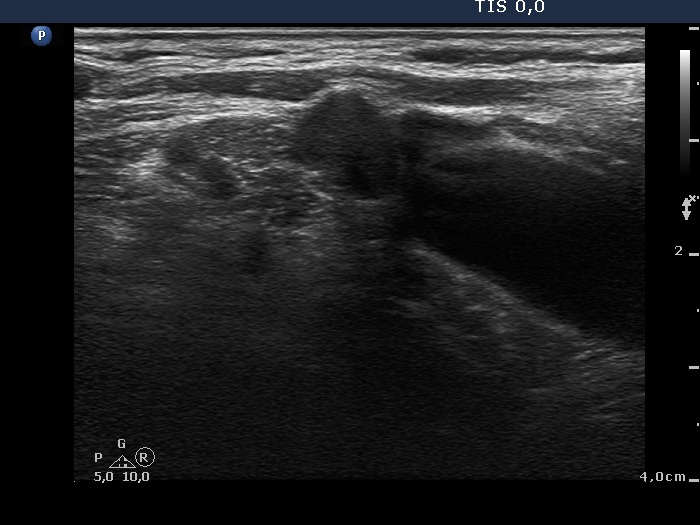

Ultrasonography: the right thyroid was echonormal while the left lobe contained moderately hypoechogenic areas with a 50% echogenicity index. There was a hypoechogenic mass lower and lateral to the right thyroid. The lesion did not present a regular hilum.